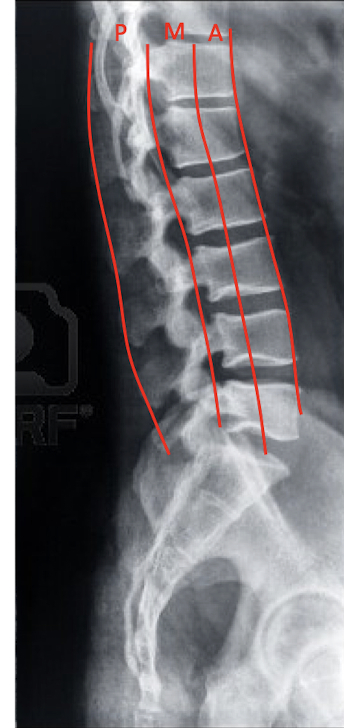

Define the 3 Column Concept:

Anterior Column

Middle Column

Posterior Column

3 Column Concept:

What structures are included in:

Anterior Column:

2

Middle Column:

2

Posterior Column:

4

Anterior Column

Anterior Longitudinal Ligament

Ant. 2/3 of Vertebral Body

Middle Column

Posterior 1/3 of the Vertebrae

Posterior Longitudinal Ligament

Posterior Column

Posterior Ligament Complex

Vertebral Arch

Facets

Ligamentum Flavum

Spinal Column Rules:

What are the 3 Spinal Column Rules?

Spinal Cord and Canal are located Posterior to the Middle Column in the Posterior Column

Fx in the Posterior and Middle Column have potential to encroach on the Spinal Cord and Canal

MRI is needed to determine the level of injury, if any, to the spinal cord

Three Column Concept:

Fractures involving ONE COLUMN are ___.

Fractures involving THREE COLUMNS are ___.

Fractures involving TWO COLUMNS depends on what? (2)

If the Middle Column is Intact, it is usually a ___ injury.

One Column:

Stable

Three Columns:

Unstable

Two Columns

May or may not be unstable

Depends on the severity of the injury

Middle is intact

Stable